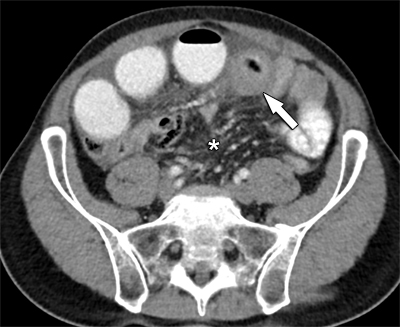

Computed tomography (CT) confirmed a large mesenteric tumoral mass extending towards the ileum, where circumferential small bowel wall invasion caused intestinal obstruction (Figures 1 and 2). There was only a moderate amount of ascites. No signs of peritoneal carcinomatosis, distant metastases or free intra-peritoneal air were present.

Figure 1

Axial view of contrast-enhanced CT reveals circumferential small bowel wall distention (arrow) and engorged mesenteric vessels (*).